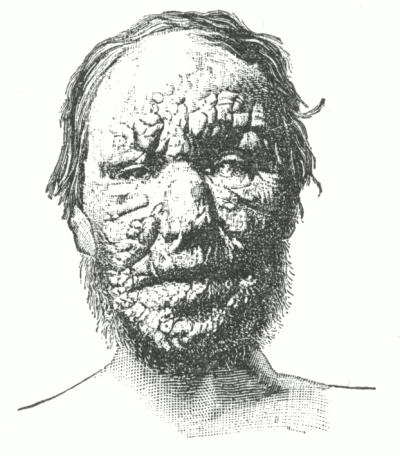

Give frequency and types of cutaneous disturbance following the administration of the bromides (bromine).